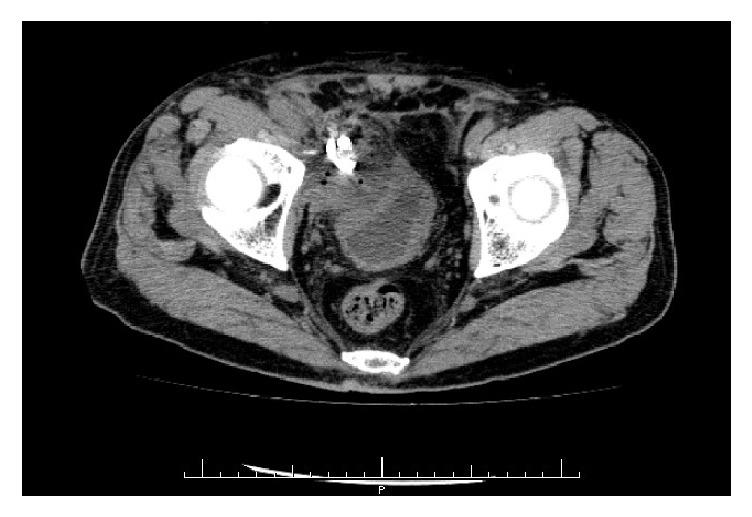

Pelvic lymphoceles are an infrequent complication after pelvic surgery and develop shortly after the surgery in most cases. We experienced a case of delayed infection of a lymphocele 6 months after robot-assisted radical prostatectomy (RARP) and pelvic lymphadenectomy. In this case, antimicrobial chemotherapy and percutaneous drainage were effective, and there was no recurrence of the disease. Most urologists do not recognize that infected lymphoceles can develop a long time after surgery; thus, infected lymphoceles should be kept in mind in patients with nonspecific infectious symptoms, regardless of the length of time after surgery.